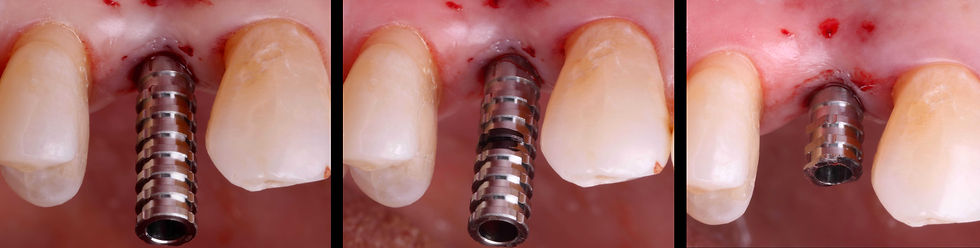

Clinical view of the positioning of the neck of the Prama RF implant. The implant connection is placed about 1 mm below the gingival margin.